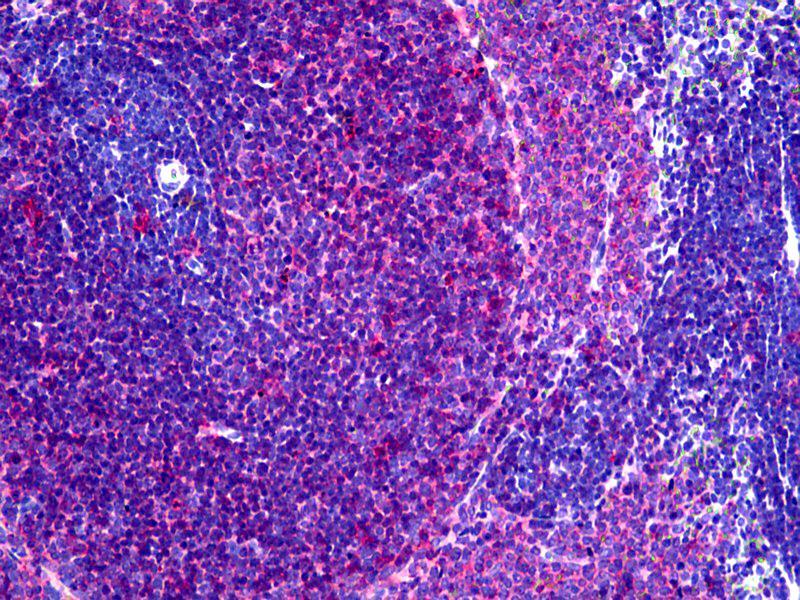

The Mouse Monoclonal anti-MHC Class II RT-1B antibody is suitable to detect MHC Class II RT-1B in samples from Rat and Mouse. It has been validated for FACS, IHC (fro), IHC (p), WB and IHC.

Flow Cytometry (FACS), Immunohistochemistry (Frozen Sections) (IHC (fro)), Immunohistochemistry (Paraffin-embedded Sections) (IHC (p)), Western Blotting (WB), Immunohistochemistry (IHC)

Recognizes a monomorphic determinant of the rat I-A antigen present on B lymphocytes, dendritic cells, some macrophages and certain epithelial cells. Reacts with certain mouse strains of MHC haplotypes k and s. Analysis of recombinant mouse strains showed that the determinants mapped to the I-A region. Does not react with the BDIX rat strain. Expression is polymorphic in mice. This product is routinely tested in flow cytometry on rat splenocytes.

Approved: Flo (1:50 - 1:100), IHC, IHC-Fr, IHC-P (10 μg/mL), WB

Usage: Flow Cytometry: Use 10 μL of the suggested working dilution to label 10^6 cells in 100 μL. Method sheets are available on request. Immunohistology: This product does not require antigen retrieval using heat treatment or protein digestion prior to staining of formalin-fixed paraffin-embedded sections, but results may be enhanced with heat treatment using 0.01M citrate buffer  pH 6.This clone has also been described reacting with paraffin-embedded material following PLP fixation (periodate-lysine-paraformaldehyde)